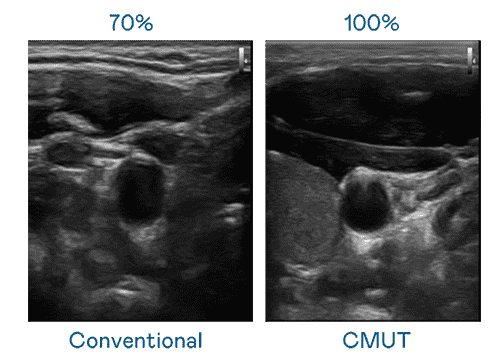

CMUT 技术是一种用电容式微机电元件来产生超音波讯号的技术。。。与传统 PZT 压电式技术相比,,,CMUT 频宽增加 30%,,,,更宽频的超音波讯号让影像解析度大幅提升,,是实现高影像品质医疗超音波扫描、、促进精准医疗发展的关键技术。。

大频宽带来超清晰影像

超音波影像的解析度高低,,,,首先取决于探头能发出的讯号频宽。。。尊龙z6 CMUT 可提供高清晰的超音波讯号,,提供高频宽、、、高灵敏度、、影像纹理细节更高的超音波影像,,协助医护人员缩短影像判读时间及利用精准的医疗影像进行诊断。。。。